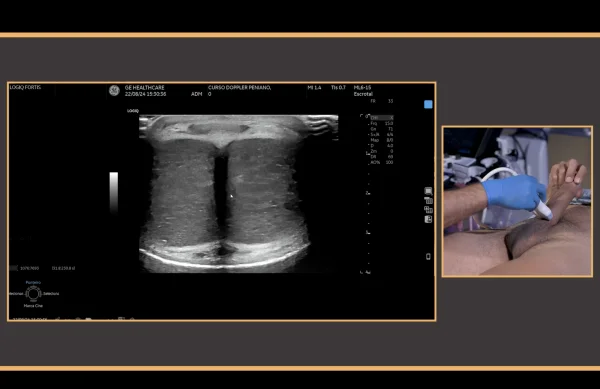

* PDU is the gold standard diagnostic modality in the vascular assessment of erectile function, and it is useful in the therapeutic decision-making process for patients with erectile dysfunction.

This video provides a step-by-step guidance in the conduction of hemodynamics studies using penile Doppler ultrasound (PDU). PDU is the gold standard diagnostic modality in the vascular assessment of erectile function, and it is useful in the therapeutic decision-making process for patients with erectile dysfunction. The video outlines the most important principles for an adequate exam conduction, which includes redosing of vasoactive agents for during erection induction, a rigidity-based assessment of hemodynamic parameters, and an effective detumescence protocol using reversal agents. The conduction of standard PDU examination of a 54 year-old man with erectile dysfunction is described.